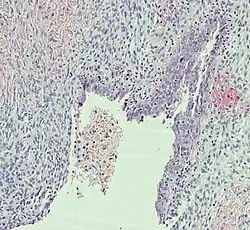

Histopathology

In case an ovarian cyst is surgically removed, a more definite diagnosis can be made by histopathology:

| Type | Subtype | Typical microscopy findings | Image |

| Functional cyst | Follicular cyst |

|

| Corpus luteum cyst |